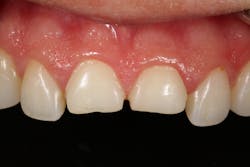

In addition to optimal bonding, the rubber dam may retract the tissues when placed properly, improving our visualization of finish lines, margins, and adhesive materials. One of dentistry’s rubber dam advocates, Dr. Hunter Brinker (the inventor of the B1-B6 clamps), often said “to see is to know” when referring to the benefits of the rubber dam to improve attention to detail through better visual access. It is interesting to note that when the rubber dam is properly placed, it will not only retract the tongue, lips, and cheeks, but it will also atraumatically retract the gingiva, typically 2–3 mm, and expose areas that could not be visualized by any other nonsurgical means (figures 3–5).